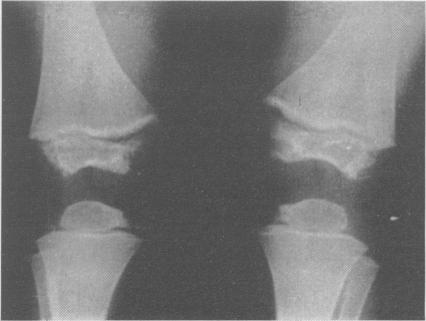

Precocious sexual development in an untreated cretin.